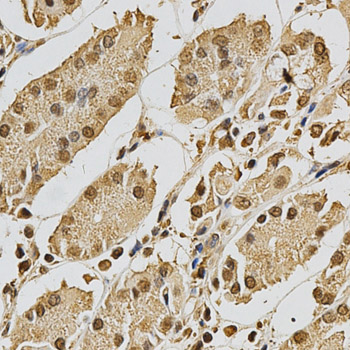

Facts about DNA repair protein XRCC3.

Nucleus. Cytoplasm. Cytoplasm, perinuclear region. Mitochondrion. Accumulates in discrete nuclear foci prior to DNA damage, and these foci persist throughout the time course of DNA repair.